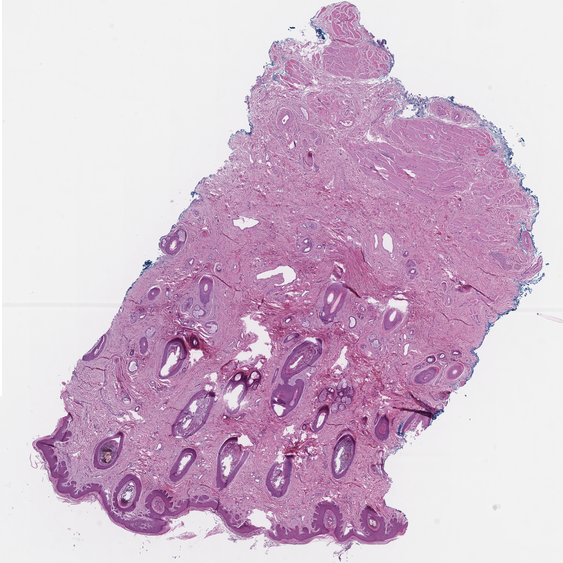

Category Train Validation Image Example

(Count) 1271 317 [Uncaptioned image]

(No-Count) Lipomas 703 176 [Uncaptioned image]

(No-Count) Non-neoplastic lesions 400 100 [Uncaptioned image]

(No-Count) Skin punch biopsies 180 45 [Uncaptioned image]

(No-Count) Skin&subcutaneous tissues 522 131 [Uncaptioned image]

Table 1: Biopsy slide classification data